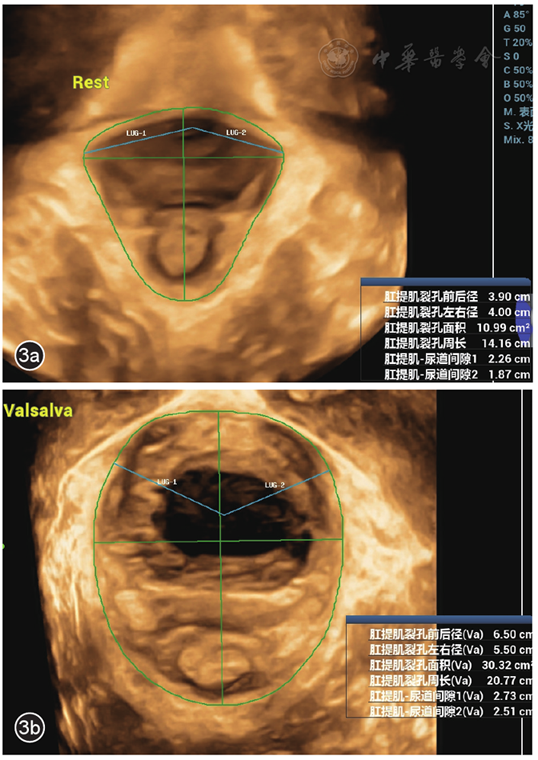

(1)手动测量:共4位经过盆底超声系统培训的医师进行手动测量,其中2位为盆底超声检查经验不足1年的年轻医师1和2(年轻医师组),另2位为盆底超声检查经验超过5年的高年资医师3和4(高年资医师组)。2组医师互相独立手动调节原始三维容积图像的三维感兴趣区下缘,经过SP下缘和PR前缘获得最小LH平面,并在该平面测量以下6项参数:面积(两侧PR内侧缘、两侧耻骨支和SP下缘围成的面积)、周长(面积所在范围的周长)、前后径(SP下缘中点与PR后缘最低点之间的距离)、左右径(LH的最大横径)、左侧肛提肌尿道间隙(左侧肛提肌附着点与尿道中心的距离)、右侧肛提肌尿道间隙(右侧肛提肌附着点与尿道中心的距离,图2),并记录从开始获取最小LH平面至测量6项参数结束所用的检查耗时。(2)自动测量:由另一位年轻医师5(自动测量组)应用FSPFU软件进行两次自动测量,在原始三维容积图基础上点击超声仪器操作屏的"自动盆底"键,即可获取最小LH平面及上述6项参数(图3)。两次自动测量间隔的时间至少2周以上,并且每次测量的图像都是原始三维容积图。记录从按下"自动盆底"键至获得6项参数的检查耗时。

图3 肛提肌裂孔(LH)全栈式自动盆底超声(FSPFU)图像。图a为FSPFU软件自动测量静息状态下LH;图b为FSPFU软件自动测量Valsalva动作下LH

注:LUG-1为右侧肛提肌尿道间隙;LUG-2为左侧肛提肌尿道间隙